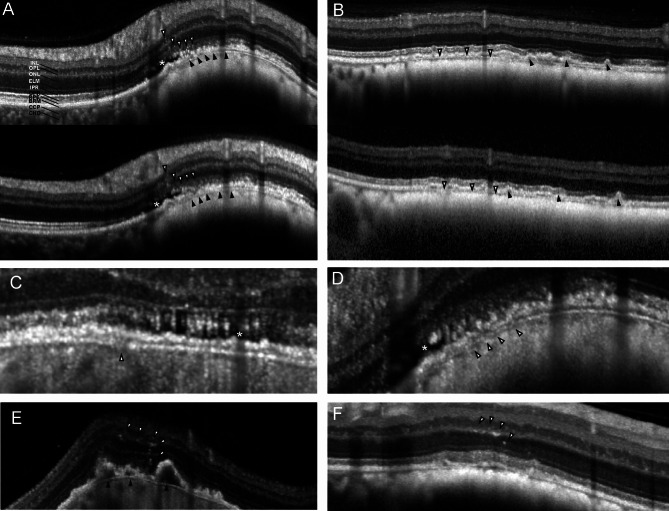

目的:评估高分辨率光学相干断层扫描(HR-OCT)与标准光谱域 OCT 在色素性脉络膜病变中的应用:我们共筛查了40名患有色素性脉络膜病变的受试者。我们用HR-OCT和标准OCT设备对病变部位进行了成像,包括增强深度成像(EDI)模式和非增强深度成像(EDI)模式。对图像进行定性和定量分级,如脉络膜压缩和宽度、脉络膜反射率和厚度等:结果:40 名受试者中有 32 名可以进行图像分析,其余受试者因成像不足而被排除在外。HR-OCT EDI模式可观察到11个病变(11/32 = 34.4%)的脉络膜后部范围,而正常HR-OCT(n = 32)、标准OCT(n = 30)和OCT EDI模式(n = 30)分别有6个病例(6/32;18.8%)、4个病例(4/30;13.3%)和5个病例(5/30;16.7%)可观察到脉络膜后部范围,尽管差异不大。10例患者在HR-OCT上出现明显的绒毛膜压缩,在所有成像模式下同样可见。平均绒毛膜厚度为 11.6 至 13.9 微米(标清范围为 3.84 至 4.33),压缩的绒毛膜厚度同样为平均 7.1 至 7.8 微米(标清范围为 2.20 至 3.55)。在四种模式中,有三种模式的图像质量向周边明显下降(p = 0.0077 至 p = 0.29):结论:HR-OCT可以更好地显示色素性脉络膜病变中的视网膜和脉络膜结构,但在尝试对周边病变成像时,图像质量会下降:HR-OCT原型可深入了解色素性脉络膜病变的临床特征,而这些特征在传统的OCT成像中并不明显。这支持了HR-OCTolution OCT设备的开发。

Methods: We screened a total of 40 subjects with pigmented choroidal lesions. Lesions were imaged on HR-OCT and standard OCT devices with and without enhanced depth imaging (EDI) mode. Images were graded for qualitative and quantitative aspects, like choriocapillaris compression and width, choroidal reflectivity and thickness, amongst others.

Results: 32 of the 40 subjects could be included in the image analysis, the rest were excluded due to insufficient imaging. HR-OCT EDI mode allowed visualization of the posterior choroidal extent in 11 lesions (11/32 = 34.4%) versus in six (6/32; 18.8%), four (4/30; 13.3%), and five cases (5/30; 16.7%) in normal HR-OCT (n = 32), standard OCT (n = 30) and OCT EDI mode (n = 30), respectively, albeit not significantly different. Choriocapillaris compression was evident in 10 cases on HR-OCT and equally visible in all imaging modes. Mean choriocapillaris thickness ranged from 11.6 to 13.9 microns (SD range 3.84-4.33), and compressed choriocapillaris thickness similarly ranged from a mean of 7.1 to 7.8 microns (SD range 2.20-3.55). Image quality declined significantly towards the periphery in three out of four modes (p = 0.0077 to p = 0.29).

Conclusions: HR-OCT may provide better visibility of retinal and choroidal structures in pigmented choroidal lesions, although image quality is reduced in attempting to image peripheral lesions.

Translational relevance: The prototype HR-OCT offers insights into clinical features of pigmented choroidal lesions that are not apparent on conventional OCT imaging. This supports the development of HR-OCTolution OCT devices.